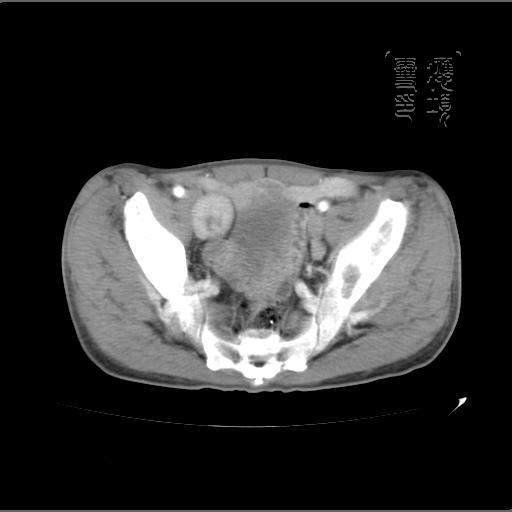

以下是引用余辉在2007-4-20 20:03:00的发言:[br]没头绪,猜一个吧,距离血管鞘近,就猜神经鞘瘤,中心部分变性囊变,另外请哪能位老师指点腹直肌后方及后外方强化物是何

以下是引用dyqct在2007-4-20 20:51:00的发言:[br]考虑:1、右侧膀胱外上方实性富血管性肿瘤(神经鞘膜瘤?纤维瘤?巨淋巴结增生症?)[br] 2、请标识需要解释的地方。

以下是引用aa13877358820在2007-4-21 7:01:00的发言:[br]隐睾?